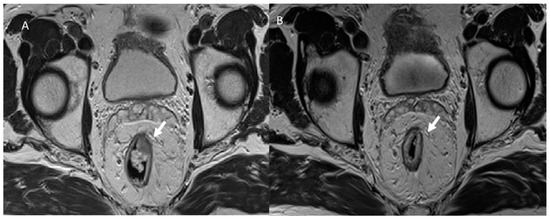

3.4. Urological Injury